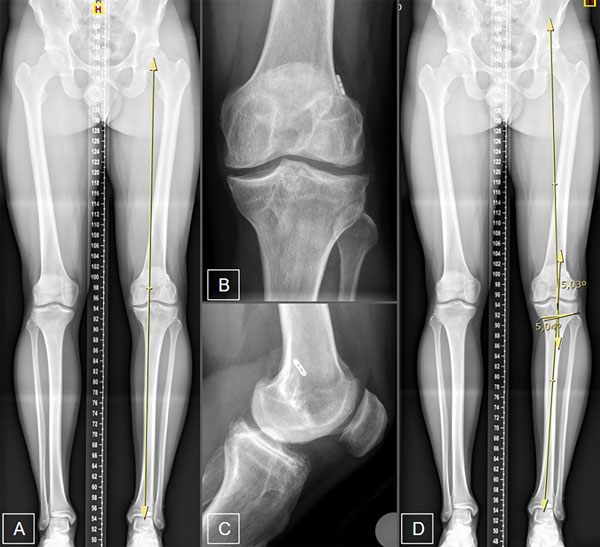

Se solicitó una radiografía panorámica de ambos miembros inferiores junto con radiografías de frente y perfil de ambas rodillas y axial de ambas rótulas (fig. 1). El eje mecánico se representó con una línea que va desde el centro de rotación de la cabeza femoral hasta el centro del domo astragalino.9 Dicho eje se calculó según el porcentaje del ancho de la meseta tibial en la cual el eje la atraviesa: 0% en el borde medial y 100% en el borde lateral. Se calificó deseje en varo cuando dicho eje se situó medial a la espina tibial medial o a más del 41% de la meseta tibial10 (ver fig.1).

La planificación preoperatoria para la osteotomía valguizante de tibia para pacientes con artrosis del compartimento medial tiene como objetivo restablecer el eje mecánico mediante la corrección en el vértice de la eminencia tibial lateral, coincidiendo con el 56% de esta. El ángulo de corrección requerido en el plano coronal se calculó trazando una línea desde el centro de la cabeza femoral hacia el vértice de la espina tibial lateral y otra línea desde el centro de la cúpula astragalina hacia el mismo vértice. El ángulo formado por su intersección representa el ángulo de osteotomía de apertura necesario para corregir el deseje. Este ángulo se transpone a la ubicación del corte más lateral de la osteotomía planificada en la tibia proximal y se expande a la tibia proximal medial. Esta angulación calculada crea un triángulo, con la altura (en milímetros) en la cortical tibial medial que representa la cantidad necesaria de corrección para la osteotomía9 (ver fig.1).

Figura 1: Planificación radiográfica. A) Eje mecánico en varo. B) Radiografía de rodilla frente. C) Radiografía de rodilla de perfil. D) Planificación de osteotomía con corrección de 5°.